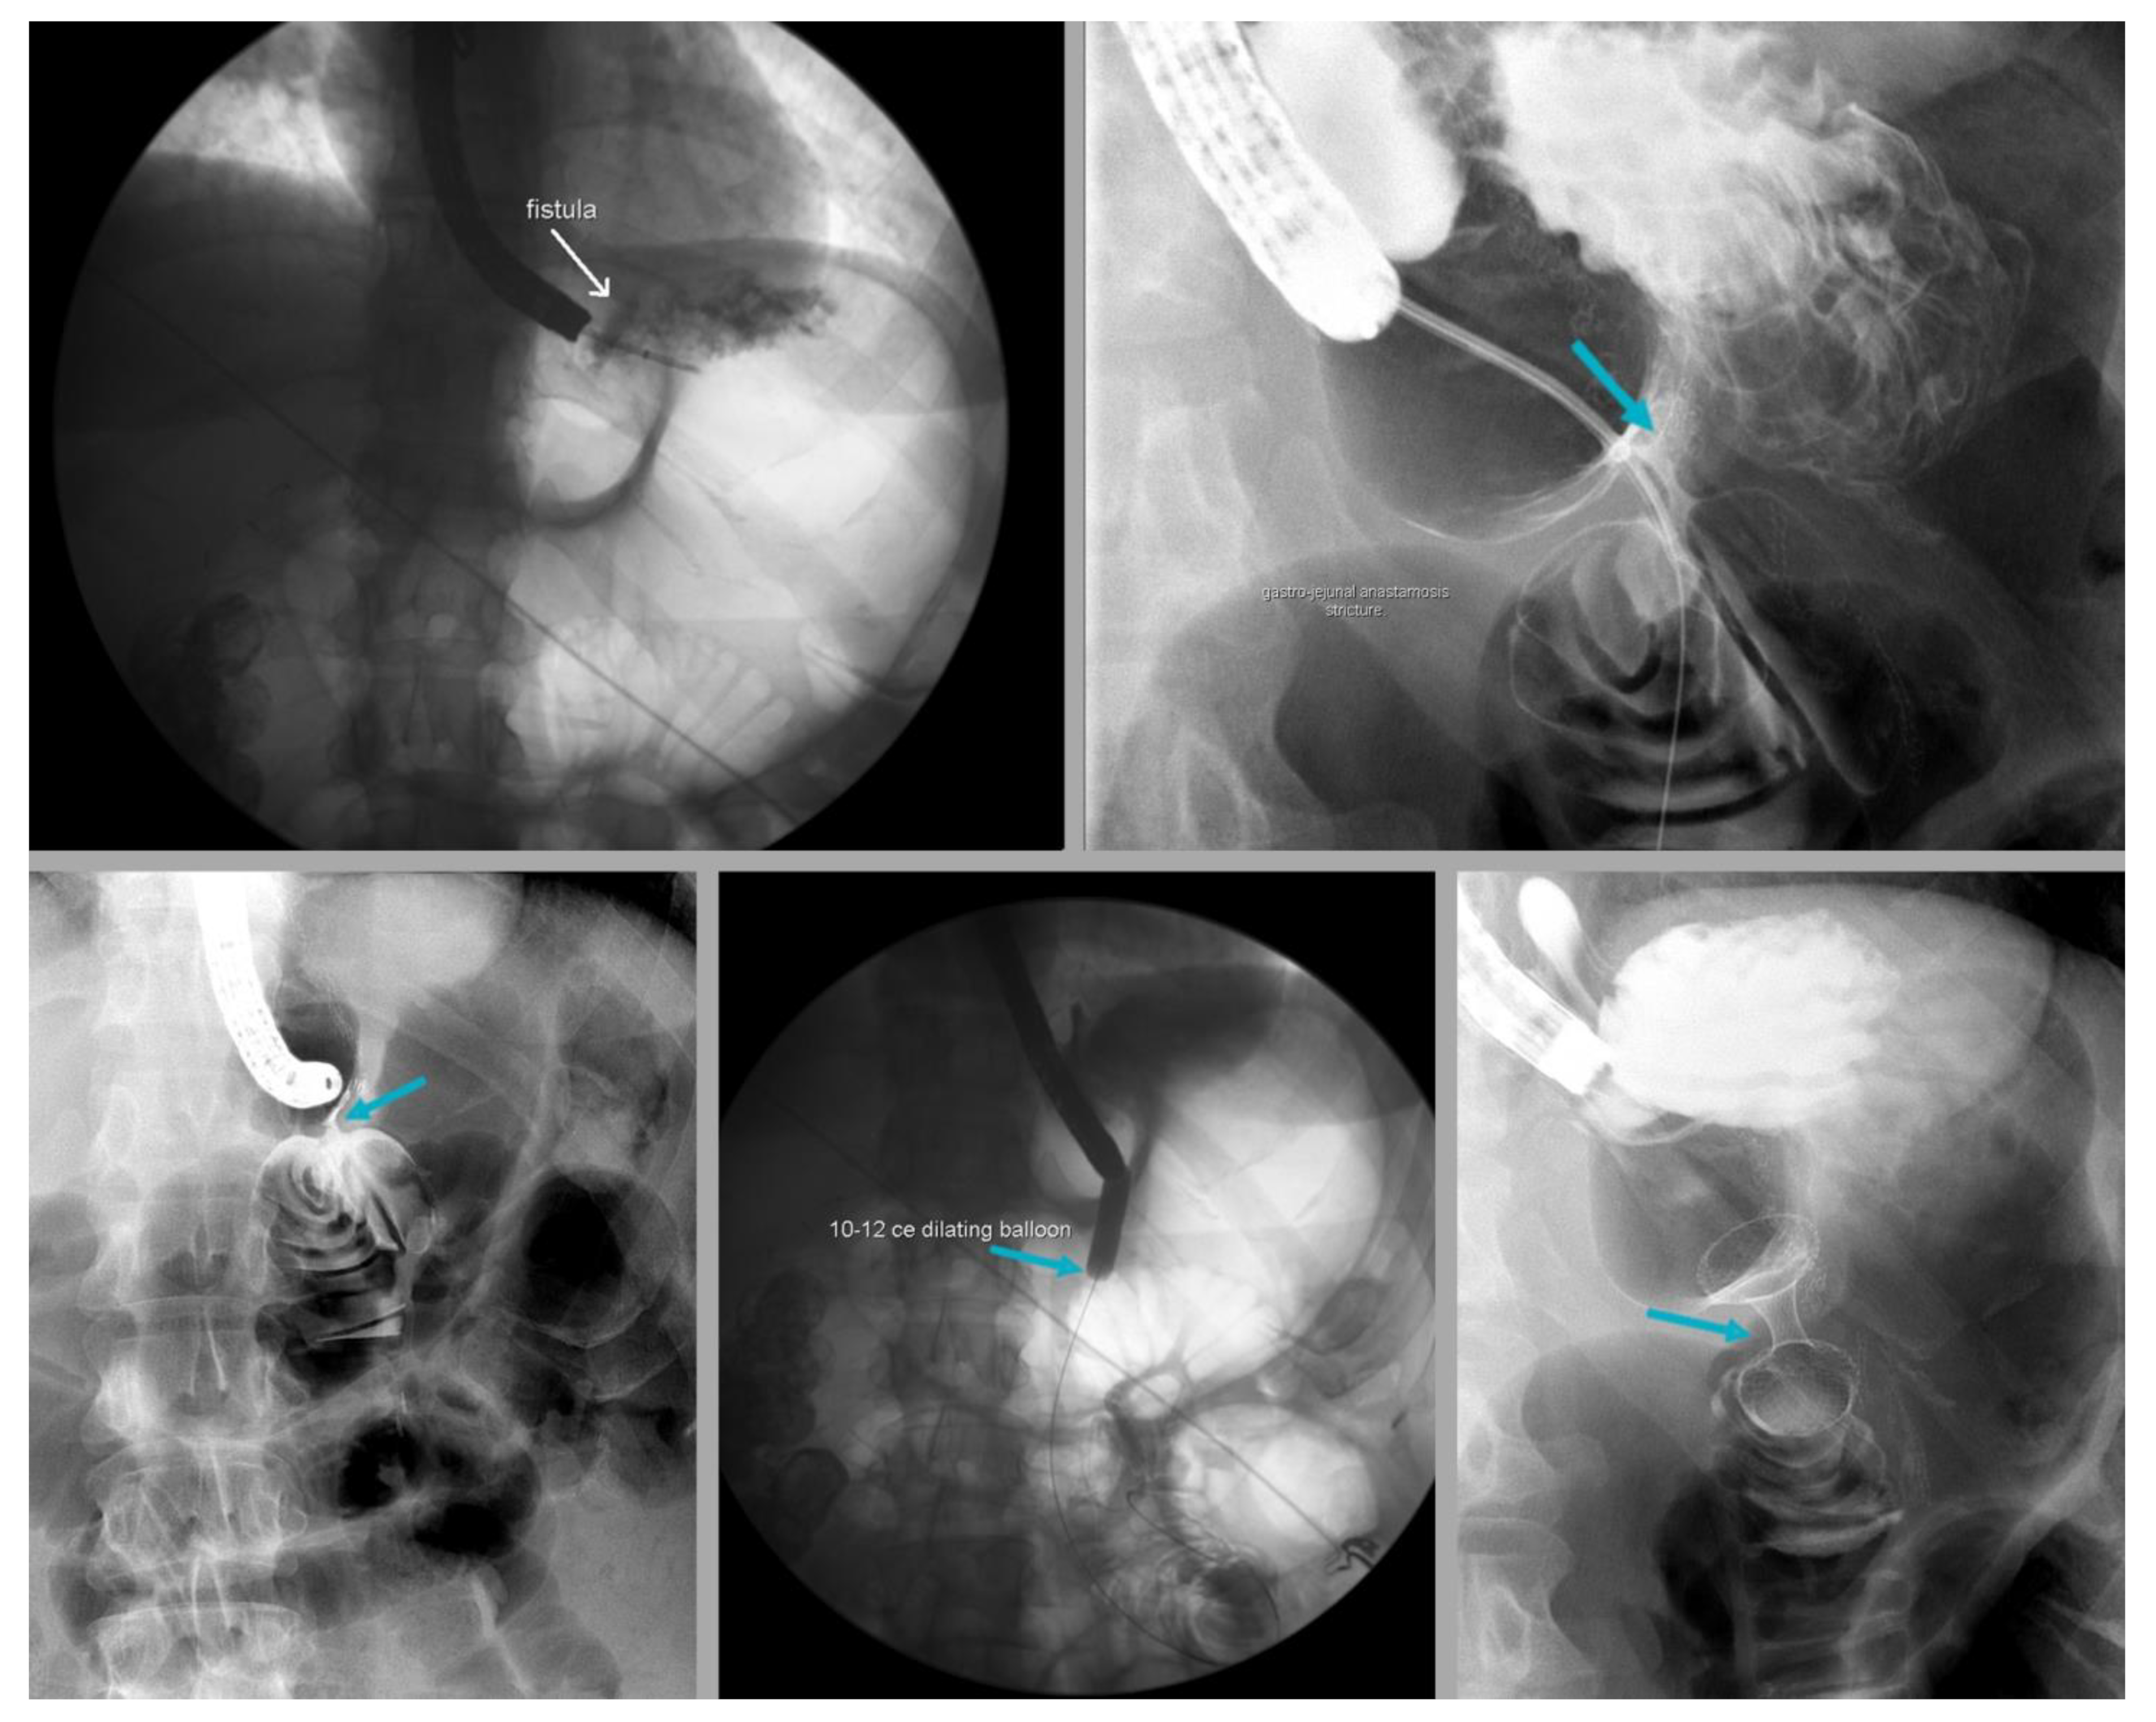

- Levy, J.L.; Levine, M.S.; E Rubesin, S.; Williams, N.N.; Dumon, K.R. Stenosis of gastric sleeve after laparoscopic sleeve gastrectomy: Clinical, radiographic and endoscopic findings. Br. J. Radiol. 2018, 91, 20170702. [Google Scholar] [CrossRef]

- Chang, S.H.; Popov, V.B.; Thompson, C.C. Endoscopic balloon dilation for treatment of sleeve gastrectomy stenosis: A systematic review and meta-analysis. Gastrointest. Endosc. 2020, 91, 989–1002.e4. [Google Scholar] [CrossRef]

- Mazer, L.; Yu, J.X.; Bhalla, S.; Platt, K.; Watts, L.; Volk, S.; Schulman, A.R. Pneumatic Balloon Dilation of Gastric Sleeve Stenosis Is Not Associated with Weight Regain. Obes. Surg. 2022, 32, 1–6. [Google Scholar] [CrossRef]

- Dhorepatil, A.S.; Cottam, D.; Surve, A.; Medlin, W.; Zaveri, H.; Richards, C.; Cottam, A. Is pneumatic balloon dilation safe and effective primary modality of treatment for post-sleeve gastrectomy strictures? A retrospective study. BMC Surg. 2018, 18, 52. [Google Scholar] [CrossRef]

- Kurien, R.; Menon, S. Balloon dilation in sleeve gastrectomy stenosis: A simple solution to an occasionally tricky problem. Gastrointest. Endosc. 2020, 91, 1003–1004. [Google Scholar] [CrossRef]

- Rossi, T.R.; Dynda, D.I.; Estes, N.C.; Marshall, J.S. Stricture dilation after laparoscopic Roux-en-Y gastric bypass. Am. J. Surg. 2005, 189, 357–360. [Google Scholar] [CrossRef] [PubMed]

- Skidmore, A.P. Use of lumen-apposing metal stents (LAMS) in the management of gastro jejunostomy stricture following Roux-en-Y Gastric Bypass for obesity: A prospective series. BMC Surg. 2021, 21, 314. [Google Scholar] [CrossRef] [PubMed]

- Mansoor, M.S.; Tejada, J.; A Parsa, N.; Yoon, E.; Hida, S. Off label use of lumen-apposing metal stent for persistent gastro-jejunal anastomotic stricture. World J. Gastrointest. Endosc. 2018, 10, 117–120. [Google Scholar] [CrossRef]

- Uchima, H.; Abu-Suboh, M.; Mata, A.; Cruz, M.; Espinos, J. Lumen-apposing metal stent for the treatment of refractory gastrojejunal anastomotic stricture after laparoscopic gastric bypass. Gastrointest. Endosc. 2016, 83, 251. [Google Scholar] [CrossRef] [PubMed]

- Filho, A.J.B.; Kondo, W.; Nassif, L.S.; Garcia, M.J.; Tirapelle, R.D.A.; Dotti, C.M. Gastrogastric Fistula: A Possible Complication of Roux-En-Y Gastric Bypass. J. Soc. Laparoendosc. Surg. 2006, 10, 326–331. [Google Scholar]

- Alyaqout, K.; Almazeedi, S.; Alhaddad, M.; Efthimiou, E.; Loureiro, M.d.P. Gastrogastric Fistula after Roux-en-y Gastric Bypass: A Case Report and Review of Literature. Arq. Bras. Cir. Dig. 2020, 33, e1509. [Google Scholar] [CrossRef] [PubMed]

- Wei, M.T.; Ahn, J.Y.; Friedland, S. Over-the-Scope Clip in the Treatment of Gastrointestinal Leaks and Perforations. Clin. Endosc. 2021, 54, 798–804. [Google Scholar] [CrossRef]

- Rogalski, P.; Swidnicka-Siergiejko, A.; Wasielica-Berger, J.; Zienkiewicz, D.; Wieckowska, B.; Wroblewski, E.; Baniukiewicz, A.; Rogalska-Plonska, M.; Siergiejko, G.; Dabrowski, A.; et al. Endoscopic management of leaks and fistulas after bariatric surgery: A systematic review and meta-analysis. Surg. Endosc. 2021, 35, 1067–1087. [Google Scholar] [CrossRef]

- Niland, B.; Brock, A. Over-the-scope clip for endoscopic closure of gastrogastric fistulae. Surg. Obes. Relat. Dis. 2016, 13, 15–20. [Google Scholar] [CrossRef]

- Kumar, N.; Larsen, M.C.; Thompson, C.C. Endoscopic Management of Gastrointestinal Fistulae. Gastroenterol. Hepatol. 2014, 10, 495–502. [Google Scholar]

- Tsai, C.; Kessler, U.; Steffen, R.; Merki, H.; Zehetner, J. Endoscopic Closure of Gastro-gastric Fistula After Gastric Bypass: A Technically Feasible Procedure but Associated with Low Success Rate. Obes. Surg. 2019, 29, 23–27. [Google Scholar] [CrossRef] [PubMed]

- Sulz, M.C.; Bertolini, R.; Frei, R.; Semadeni, G.-M.; Borovicka, J.; Meyenberger, C. Multipurpose use of the over-the-scope-clip system (“Bear claw”) in the gastrointestinal tract: Swiss experience in a tertiary center. World J. Gastroenterol. 2014, 20, 16287–16292. [Google Scholar] [CrossRef] [PubMed]

- Fernandez-Esparrach, G.; Lautz, D.B.; Thompson, C.C. Endoscopic repair of gastrogastric fistula after Roux-en-Y gastric bypass: A less-invasive approach. Surg. Obes. Relat. Dis. 2010, 6, 282–288. [Google Scholar] [CrossRef] [PubMed]

- Dolan, R.D.; Jirapinyo, P.; Maahs, E.D.; Thompson, C.C. Endoscopic closure versus surgical revision in the management of gastro-gastric fistula following Roux-en-Y gastric bypass. Endosc. Int. Open 2023, 11, E629–E634. [Google Scholar] [CrossRef] [PubMed]

- Pina, L.; Wood, G.C.; Richardson, S.; Obradovic, V.; Petrick, A.; Parker, D.M. Bariatric revisional surgery for gastrogastric fistula following Roux-en-Y gastric bypass positively impacts weight loss. Surg. Obes. Relat. Dis. 2023, 19, 626–631. [Google Scholar] [CrossRef] [PubMed]

- Tsai, Y.-N.; Wang, H.-P.; Huang, C.-K.; Chang, P.-C.; Lin, I.-C.; Tai, C.-M. Endoluminal stenting for the management of leak following sleeve gastrectomy and loop duodenojejunal bypass with sleeve gastrectomy. Kaohsiung J. Med. Sci. 2018, 34, 43–48. [Google Scholar] [CrossRef]